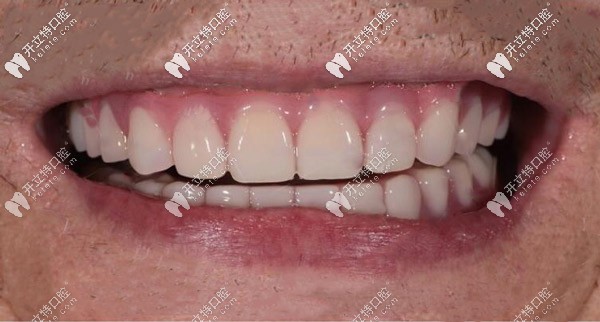

種植后▼

全口種植牙種植牙后

種植完成后口內(nèi)照片對比▼

ALL-ON-4半固定種植前后對比照

從種完牙的圖片可以看出,種植假牙比有的真牙還要好看,當然種植牙的咬合力也是比較逼近自然牙齒的,而且有了種植體的支撐可以有效緩解牙齦的吸收。